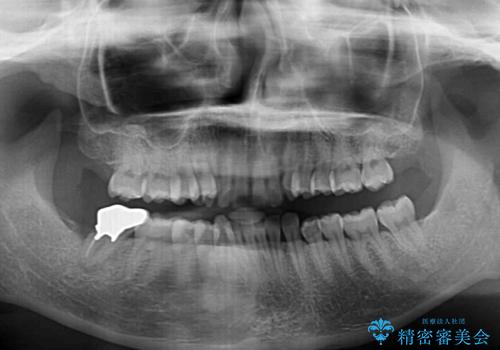

- 上顎前歯の前方に傾斜した咬み合わせを気にして来院された患者様です。

奥歯の咬み合わせを見ると、上顎が下顎に対して相対的に前方にありました。

深い咬み合わせを改善するためには、上顎臼歯を後方に移動させつつ、下顎の小臼歯を直立させる必要があります。

インビザライン単体で対応ることも検討できますが、達成する可能性が低いため、カリエールディスタライザーという補助装置を併用して、より確実性を上げることとしました。